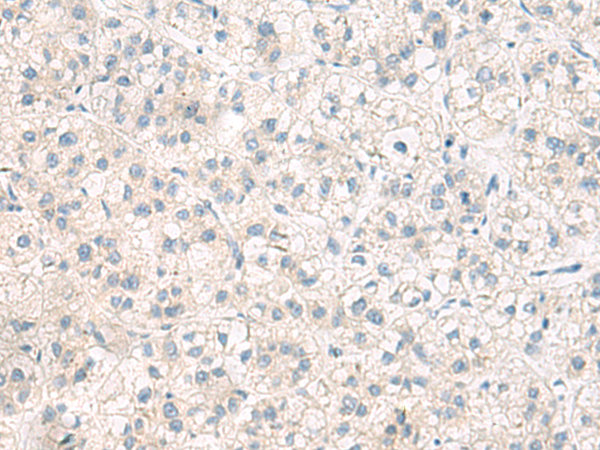

分类: 科研抗体货号: P03224别名: DROER应用: IHC反应种属: Human, Mouse

分类: 科研抗体货号: P03277别名: NS4ATP2应用: IHC反应种属: Human, Mouse

分类: 科研抗体货号: P03307别名: ATPO; OSCP; ATP5O; HMC08D05应用: WB,IHC反应种属: Human, Mouse

分类: 科研抗体货号: P03217别名: CT79; CEP4L; SPGF26应用: IHC反应种属: Human, Mouse, Rat

分类: 科研抗体货号: P03272别名:应用: WB,IHC反应种属: Human

分类: 科研抗体货号: P03298别名: L22mt; RPML25; HSPC158; MRP-L22; MRP-L25应用: WB,IHC反应种属: Human, Mouse, Rat

分类: 科研抗体货号: P03331别名: CAF1; CAF-1; Caf1a; hCAF-1应用: IHC反应种属: Human, Mouse

分类: 科研抗体货号: P03266别名: CIP; CINAP; AD-004; hCINAP; CGI-137应用: IHC反应种属: Human, Mouse, Rat

分类: 科研抗体货号: P03292别名:应用: IHC反应种属: Human, Mouse, Rat

分类: 科研抗体货号: P03325别名: PKDR1; SAMD6; NPHP16; ANKRD14应用: IHC反应种属: Human, Mouse, Rat